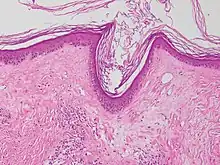

Micrograph of a vacuolar interface dermatitis with dermal mucin, as may be seen in lupus. H&E stain.

Vacuolar interface dermatitis (VAC, also known as liquefaction degeneration, vacuolar alteration or hydropic degeneration) is a dermatitis with vacuolization at the dermoepidermal junction, with lymphocytic inflammation at the epidermis and dermis.[1]